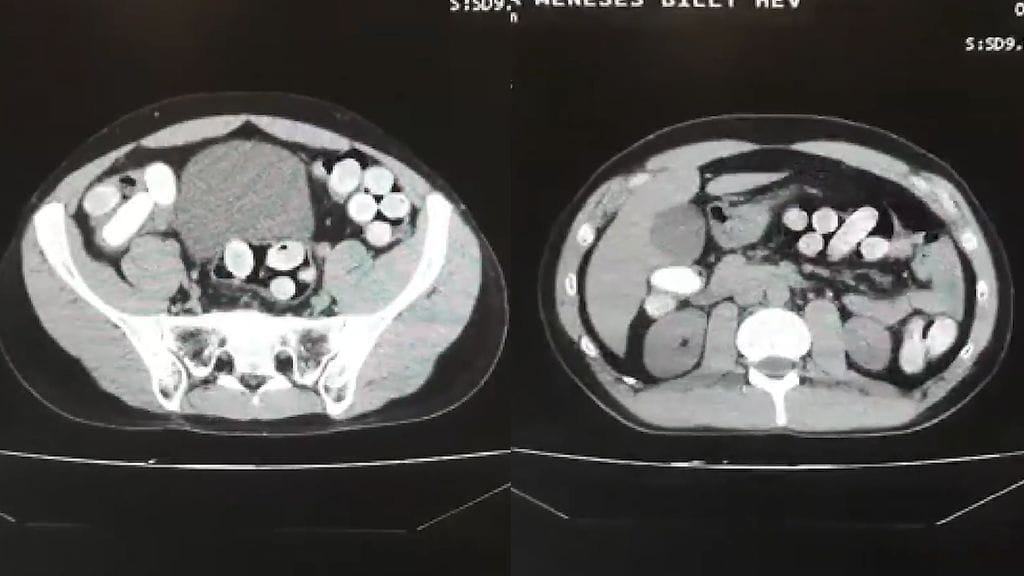

Kolme epäiltyä oli piilottanut kokaiinierän suolistoihinsa nielemällä.

Lopulta paljastui, että salakuljettajien mahoista löytyi yhteensä 190 huumekapselia sekä 24 muovipussia ainetta.

Salakuljetettava tavara paljastui epäiltyjen kehoista otetuista röntgenkuvista. Katso paljonpuhuvaa videomateriaalia yläpuolelta löytyvältä videolta.